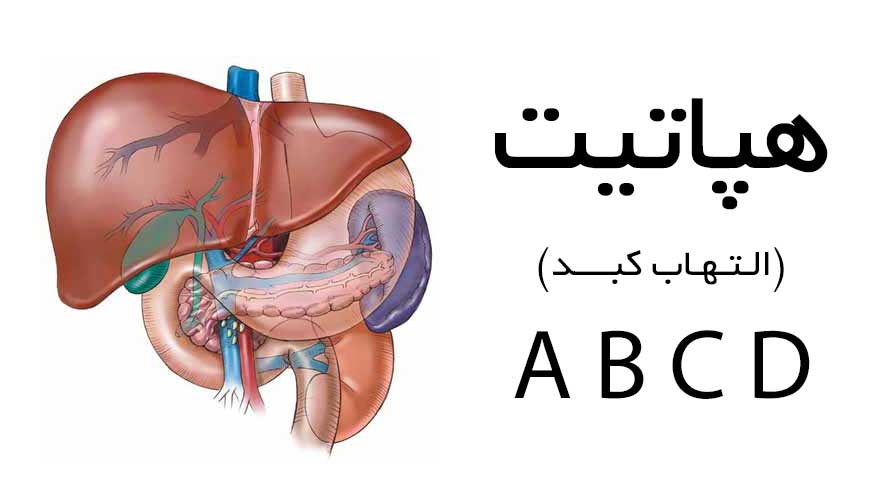

کیت های عفونی